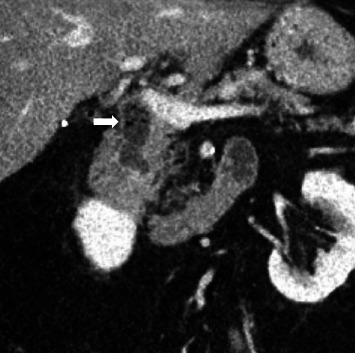

Introduction: Sump syndrome is a rare complication following bilioenteric anastomosis, most commonly following choledochoduodenostomy. This is only the third case in the literature of sump syndrome of the distal common bile duct (CBD) following end-to-side Roux-en-Y choledochojejunostomy (RYCJ). Case Presentation. A 69-year-old man with a history of end-to-side RYCJ for recurrent primary choledocholithiasis presented 3 years postoperatively with right upper quadrant (RUQ) abdominal pain affecting his quality of life. The work up revealed mild leukocytosis and computed tomography (CT) imaging that showed dilation of the distal CBD remnant. He underwent endoscopic retrograde cholangiopancreatography (ERCP) with the removal of large amounts of debris with initial resolution of his pain, but the pain recurred after several months and after two further ERCPs with only short-term resolution of pain, he eventually underwent an open distal CBD excision and the pain has since resolved.

Conclusions: This case report describes a rare case of sump syndrome following RYCJ that presented with abdominal pain alone. Sump syndrome may have a wide array of presenting symptoms, and the pathophysiology of sump syndrome varies based on bilioenteric reconstruction. Although it has rarely been reported to occur in the distal blind CBD remnant following either RYCJ or hepaticojejunostomy, it is important to consider this in the differential for patients with abdominal pain following any bilioenteric reconstruction.